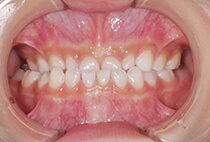

20代女性の患者さま。

八重歯の見た目が気になってご来院されましたが、実は顎の痛みや開口障害など、顎関節症の症状もありました。

そのため、かみ合わせと顎関節症の治療を同時に行ったにもかかわらず、2年間で治療が終了。

かみ合わせが整い咬筋の過緊張も改善しました。咬筋の肥大も治ってフェイスラインがすっきりしました。

最終的には美しい歯並びと、安定した痛みのないかみ合わせが実現しました。

しっかり前歯を下げるために、インプラントアンカーを使用してコントロールしました。

かみ合わせが整うと咬筋の過緊張が改善。

過緊張による筋肉肥大も改善しフェイスラインもすっきりしました。

治療前

治療後